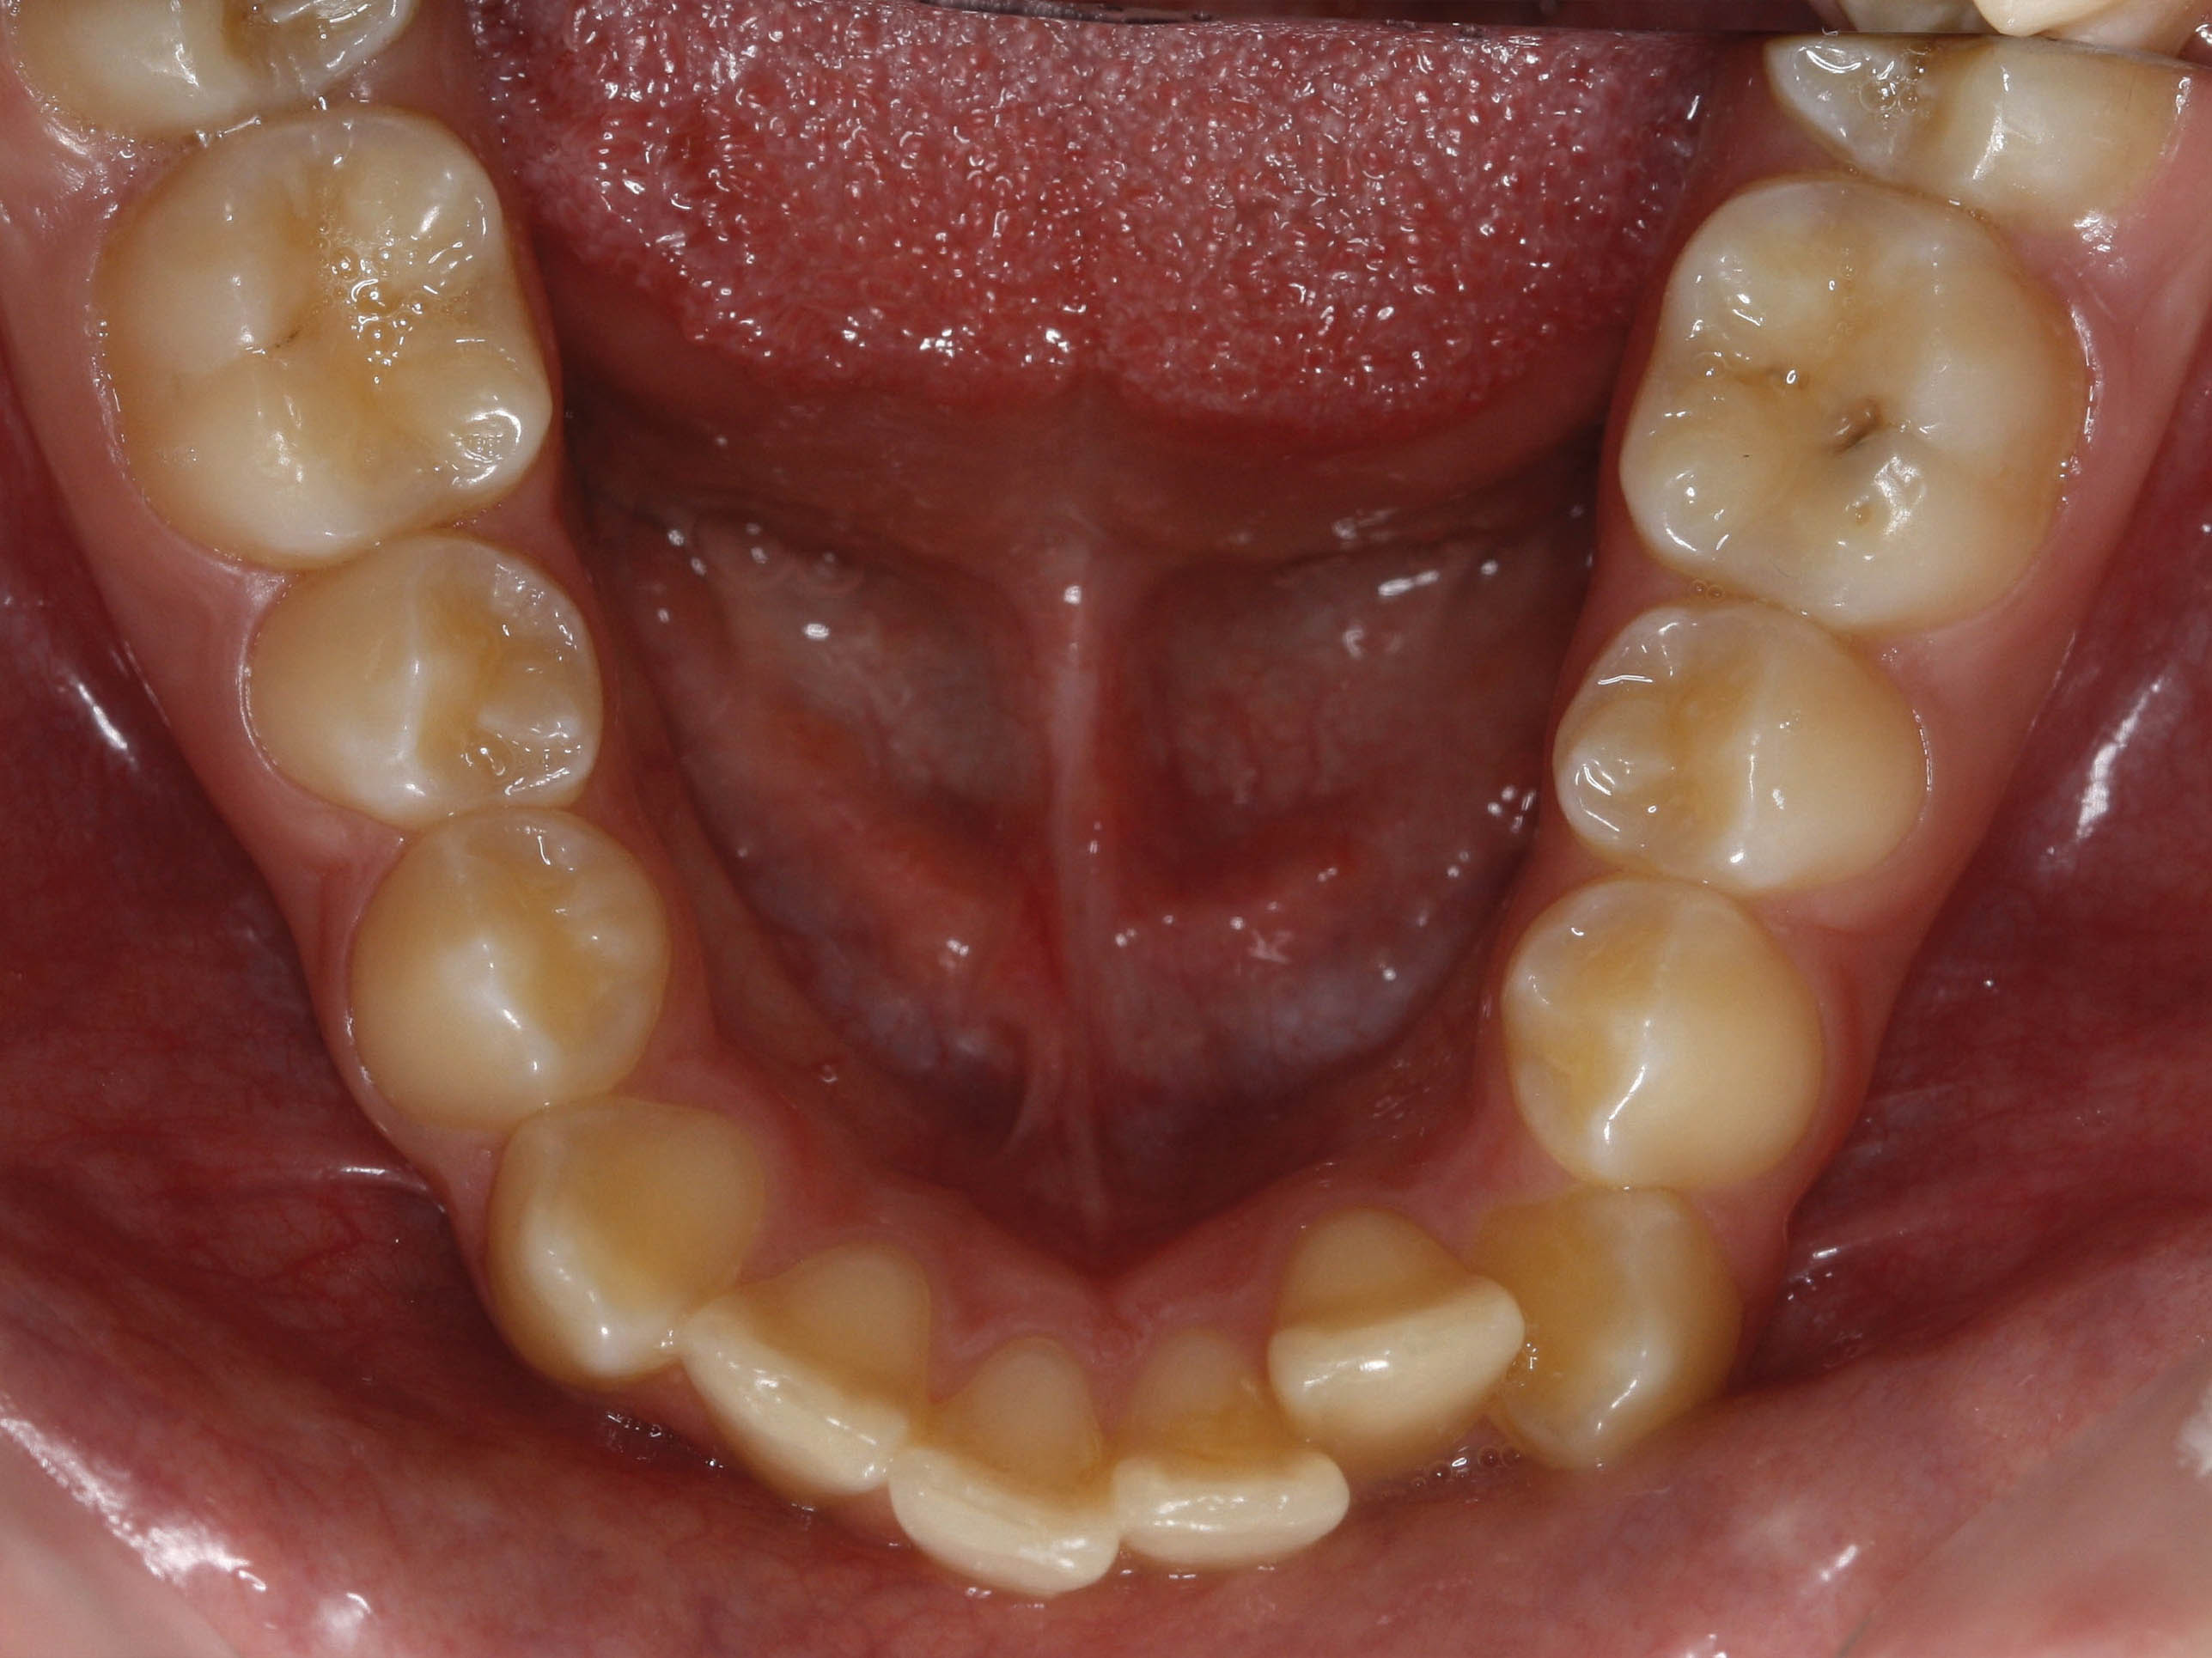

قبل از درمان